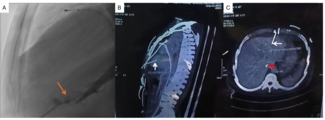

Ping Hu, MD; Xin-yu Wang, MD; Ming Qi, MD; Jie Wang, MD; Xiao-Jing Ma, PhD

A 55-year-old man presented with medically controlled essential hypertension and a history of abdominal aortic aneurysm stenting 2 years prior who presented with a 3-month history of left lower extremity fatigue on exertion.

05/04/2026